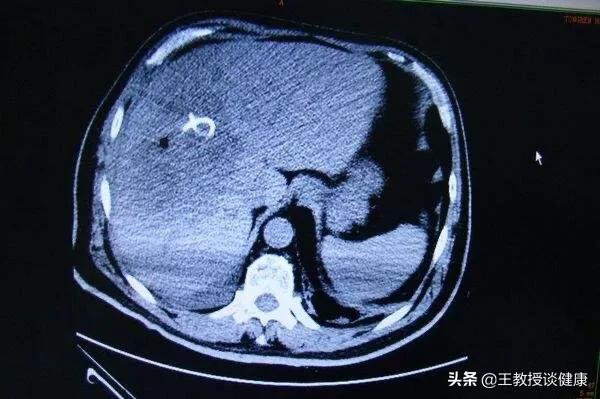

全身应用有效抗生素一周的影像

大部分未液化的细菌性肝脓肿,经过全身应用有效抗生素会慢慢消散吸收;如果经彩超或CT检查证实脓肿有明显液化,应首选经皮经肝脓肿穿刺置管冲洗引流术;非常大的,有破溃趋向的肝脓肿,应进行手术引流,置管应用抗生素;如果反复发作的肝脓肿,且局限于比较容易切除的部位,则应该进行肝脓肿切除。